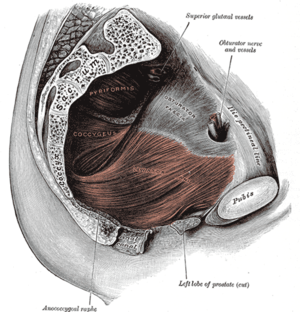

It is the loss of small amounts of urine associated with coughing, laughing, sneezing, exercising or other movements that increase intra-abdominal pressure and thus increase pressure on the bladder. The urethra is supported by fascia of the pelvic floor. If this support is insufficient, the urethra can move downward at times of increased abdominal pressure, allowing urine to pass.

One of the most common treatment recommendations includes exercising the muscles of the pelvis. Kegel exercises to strengthen or retrain pelvic floor muscles and sphincter muscles can reduce stress leakage.[6] Patients younger than 60 years old benefit the most.[6] The patient should do at least 24 daily contractions for at least 6 weeks.[6] It is possible to assess pelvic floor muscle strength using a Kegel perineometer.

Increasingly there is evidence of the effectiveness of pelvic floor muscle exercise (PFME) to improve bladder control. For example, urinary incontinence following childbirth can be improved by performing PFME.[7]